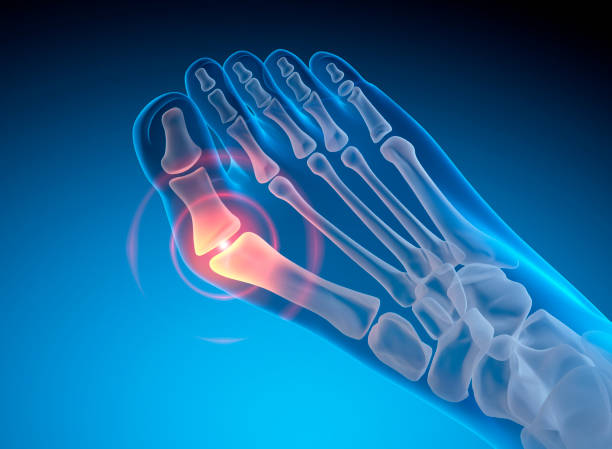

종자골염은 엄지발가락 아래쪽에 위치한 작은 뼈인 종자골(sesamoid bone)에 염증이나 통증이 발생하는 질환으로, 주로 반복적인 압력이나 충격으로 인해 발생합니다. 이 부위는 체중이 집중되는 부위 중 하나로, 보행이나 운동 시 지속적으로 자극을 받기 쉬우며, 특히 하이힐을 자주 신거나 달리기, 점프 등의 활동을 자주 하는 사람에게 잘 나타납니다. 종자골염은 초기에는 가벼운 통증으로 시작되지만, 시간이 지남에 따라 발바닥 앞쪽의 통증이 심해지고, 걸을 때 불편함을 초래하거나 발을 디딜 때 찌릿한 통증이 느껴지는 등 일상생활에 큰 영향을 미칠 수 있습니다. 본 글에서는 종자골염의 주요 원인 10가지를 중심으로, 나타나는 증상과 진단 방법, 그리고 효과적인 치료법과 재발 방지를 위한 관리법에 대해 구체적으로 살펴보겠습니다.

종자골염의 대표적인 증상은 발 앞쪽, 특히 엄지발가락 아래 부위의 통증입니다. 이 통증은 서 있거나 걷거나 뛸 때 더욱 심해지며, 장시간 활동 후에는 발바닥이 욱신거리거나 짓눌리는 느낌이 들 수 있습니다. 일부 환자는 국소적인 부기나 압통, 열감을 느끼기도 하며, 통증으로 인해 발을 절거나 무의식적으로 보행 자세가 바뀌는 경우도 있습니다. 증상이 심해지면 신발 신는 것조차 불편해지고, 심한 경우 발을 디디기 어려운 상태에 이를 수 있습니다. 특히 뻣뻣한 바닥을 맨발로 걸을 때 통증이 뚜렷해지며, 뼈를 누를 때 날카로운 통증이 느껴질 수 있습니다. 종자골염은 만성적으로 진행되는 경우가 많아 조기에 적절한 관리가 이루어지지 않으면 지속적인 통증과 활동 제한이 동반되며, 이로 인해 일상생활의 불편과 삶의 질 저하로 이어질 수 있습니다. 따라서 초기 증상을 인지하고 빠르게 대처하는 것이 매우 중요합니다.